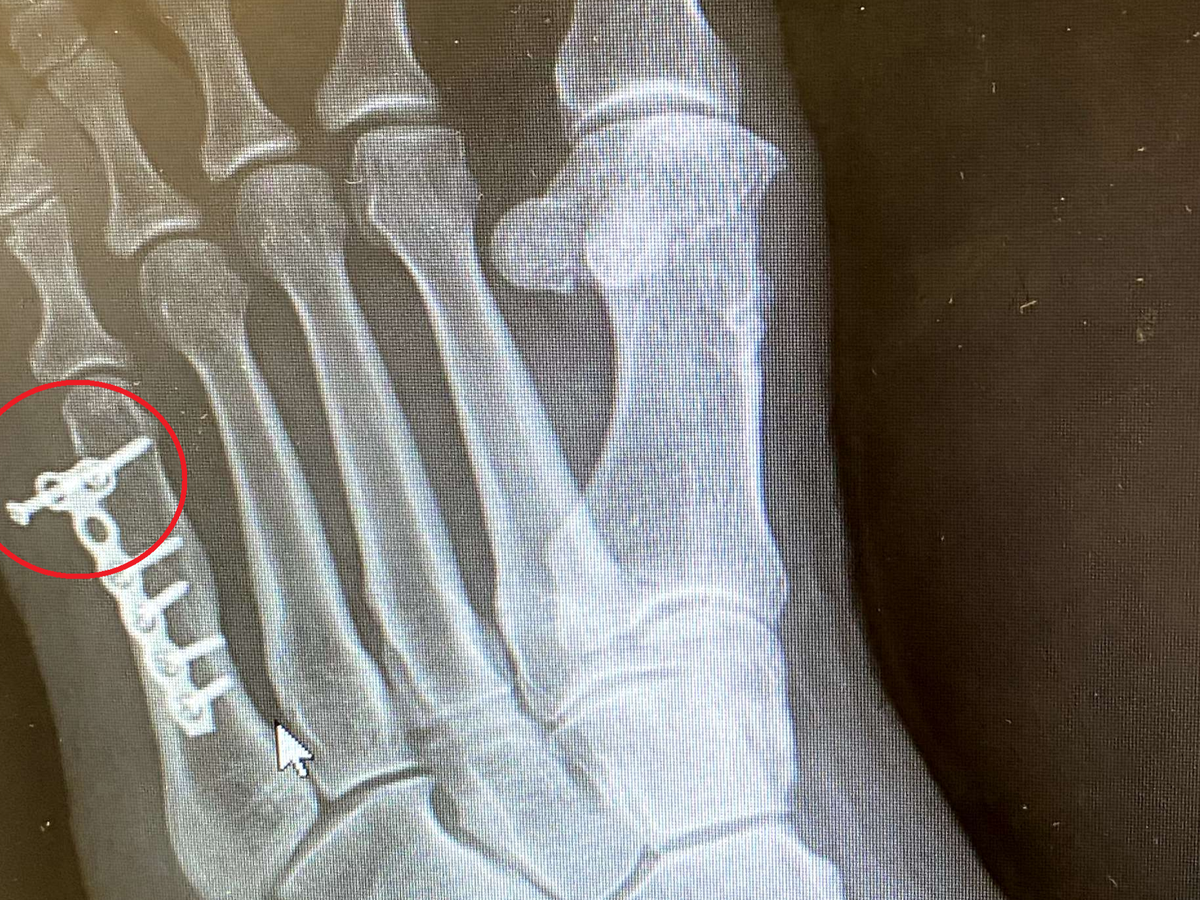

My mom needing surgery on her foot